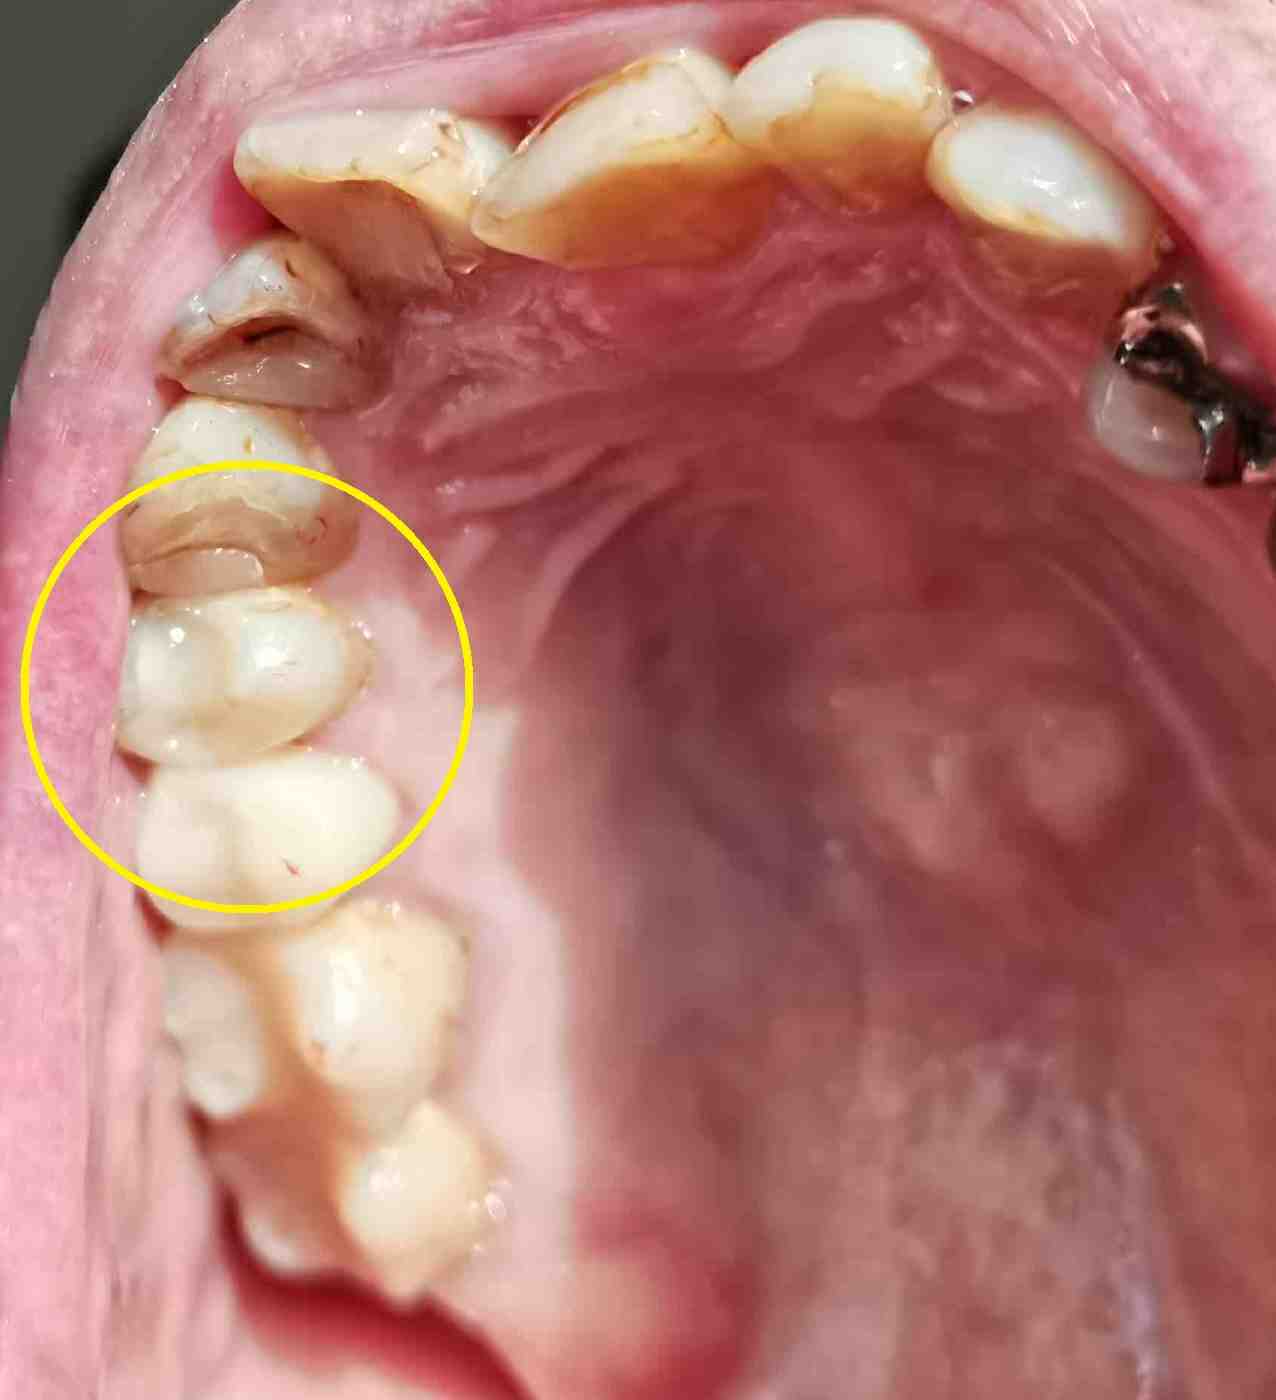

右上奥から →

3本目?

左上奥4本目、のはずが

← これ?